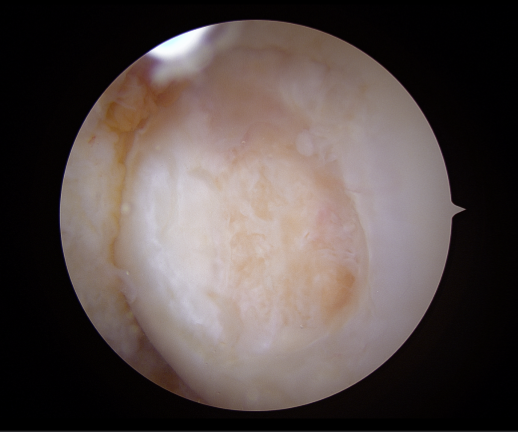

▶수술 전_관절내시경 사진 02

영상검사를 통해 확인한 소견은 비교적 명확했습니다.

- - 외측 대퇴골(LFC)에 발생한 거대 골연골박리(OCD, Osteochondral Defect)

- - 외측 반월상연골(Lateral Meniscus) 파열

- - 오른쪽 무릎의 외반 변형(Valgus knee)

특히 문제였던 것은 OCD 병변의 크기가 ‘Huge’ 수준이었다는 점입니다.